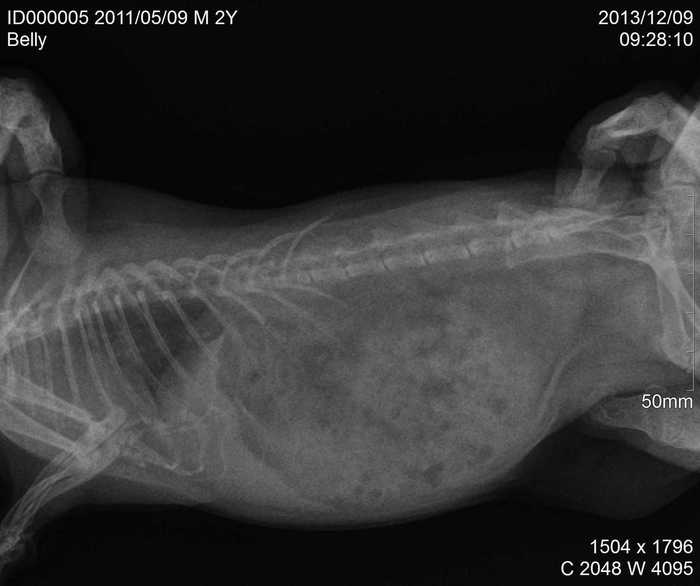

Úvod > Galerie > RTG snímky